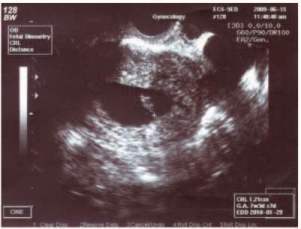

Nynější onemocnění: Pacientka přichází k potvrzení gravidity na UZ v 9. gestačním týdnu. Při UZ vyšetření byl prokázán jeden živý plod, CRL12mm, ovárium vlevo obklopeno anisochegenním útvarem o velikosti 9x5 cm, mírný ascites. Při vaginálním vyšetření byla hmatná za dělohou omezeně pohyblivá rezistence, neostře ohraničená. Pro vysokou suspekci na maligní etiologii odebrány (CA 125: 280 iu/ml, AFP a CA72-4 negativní)a provedeny stagingová vyšetření (RTG S+P a UZ epigastria negativní).